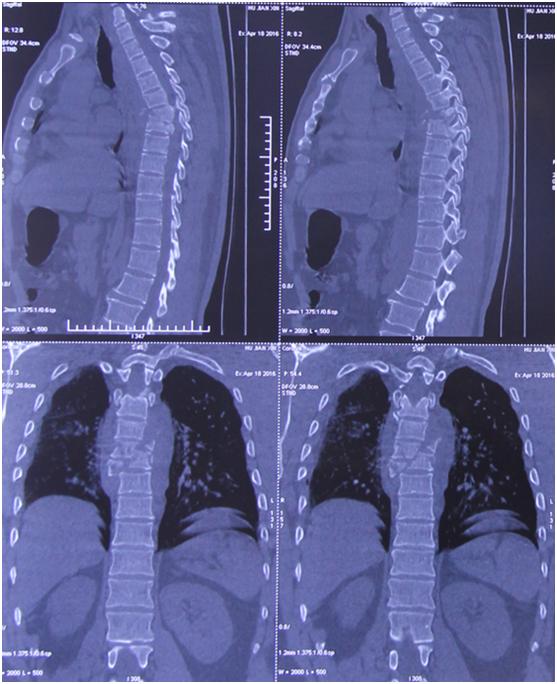

入院后,唐都医院神经外科给予高度重视,积极行术前检查。神经外科脊柱脊髓疾病治疗组组长李维新教授*析王分**先生影像学检查资料,指出“从患者影像学资料来看,1.胸6、7椎体骨折,脊髓轻度受压;2.胸6、7椎体爆裂性骨折,颈7椎体棘突骨折,左侧1、2肋骨及右侧第6肋骨骨折。”

影像学资料